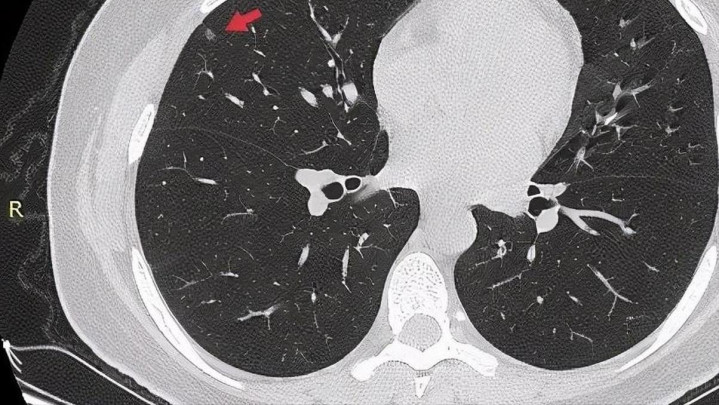

很多人以为肺结节只是个“小阴影”,忍一忍、看着它不变大就行。但医学上早已明确,不是所有结节都无害。一些微小病变在几年内就可能演变为更严重的问题,而你每天吃下去的食物,有可能正是“助火为虐”的推手。饮食的破坏力,远超你想象。

很多人以为“我又不是癌症,不用太紧张”,但医学上早已证明,小于8毫米的肺结节只要在炎症环境中反复刺激,也可能在几年内发展为不可逆的病变。而这个过程,常常悄无声息。

如果你已经查出肺结节,或者家人有类似情况,从现在开始,就把嘴管住,把肺腾空。不是不让你吃东西,而是要吃对方向。别让好心养生,变成给肺“添堵”。